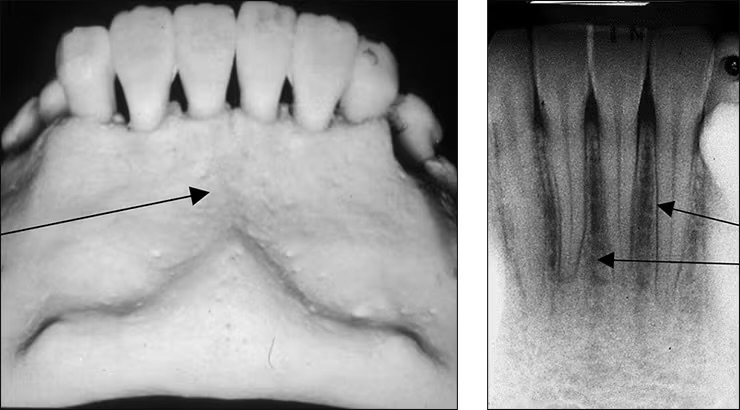

Incisive foramen / nasopalatine foramen

Appears between the roots of the central incisor & looks like a round oval less than 1 cm in diameter

Seen on maxillary central incisor PA’s

Median palatine suture

Appears as a thin vertical line in the midline on max central incisor PA’s

Is where the two halves of the maxillary come together